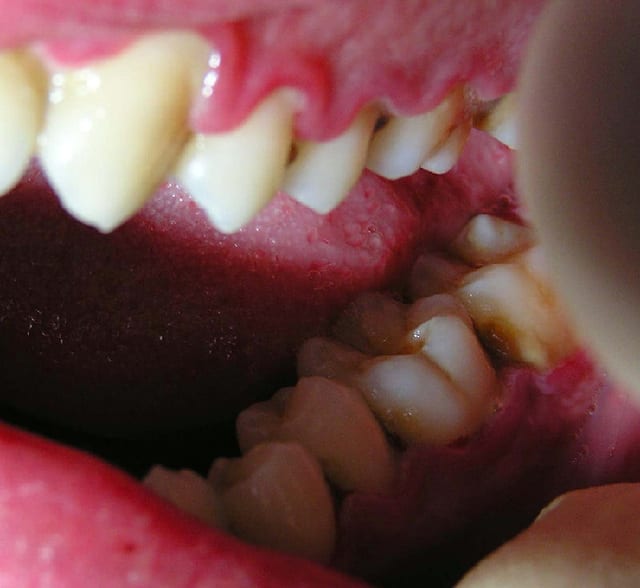

J'ai ressorti les photos prises initialement:

22/06/2005 à 02h01

La microscopie initiale de ce cas.

Pas de très belles photos car les bestioles étaient trop vivaces et comme c'était le dernier rendez-vous, je ne me suis pas senti d'attendre trois ou quatre heures que leur activité baisse...

Beaucoup de spirochètes, des trichomonas, quelques entamoebas et des hématies liées au saignement spontané.